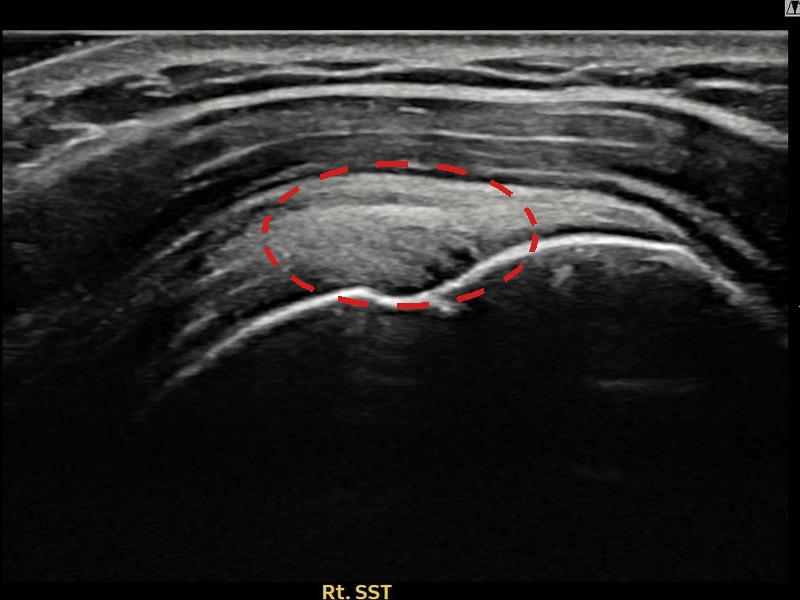

김ㅇㅇ님 · 우측 극상근건 점액낭면측 부분파열

우측 어깨 통증으로 팔을 들어올리기 어렵고 취침 시 통증이 심해 내원하셨습니다. 점액낭면측 부분파열에 대해 축소봉합술을 시행하였고 힘줄 구조가 완전히 회복되었습니다.